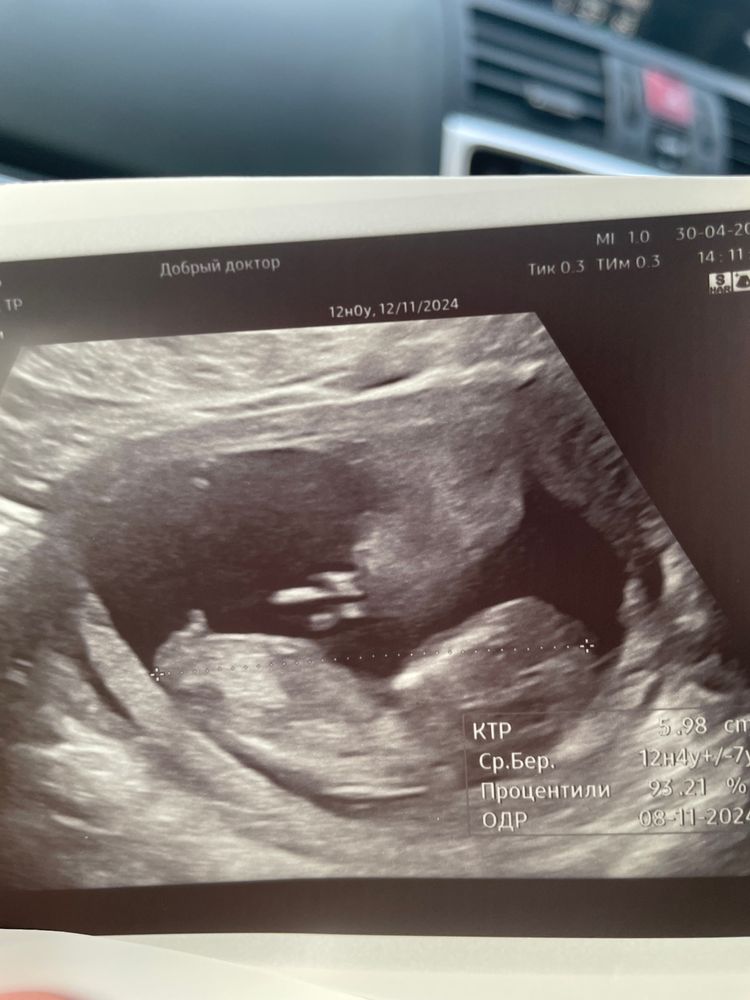

Пол ребенка на 1 скрининге

Даже в 15 недель мне сказали , что мальчик 98 % . В 17 недель мальчик стал девочкой. Я думаю недель до 18 это прям гадание на кофейной гуще с результатом 50/ 50. И у кого то просто эти 50 попадают , а у кого то нет

Ну срок и правда маленький. Мне тоже не говорили, ходила на скрининг в 12+6. Они могут ошибку допустить. Да и не видно то толком ничего ещё. В 16 недель сходите на узи, там уже все будет сформировано и чётко видно))

Пол малыша. Пол ребенка 11,6 недель.